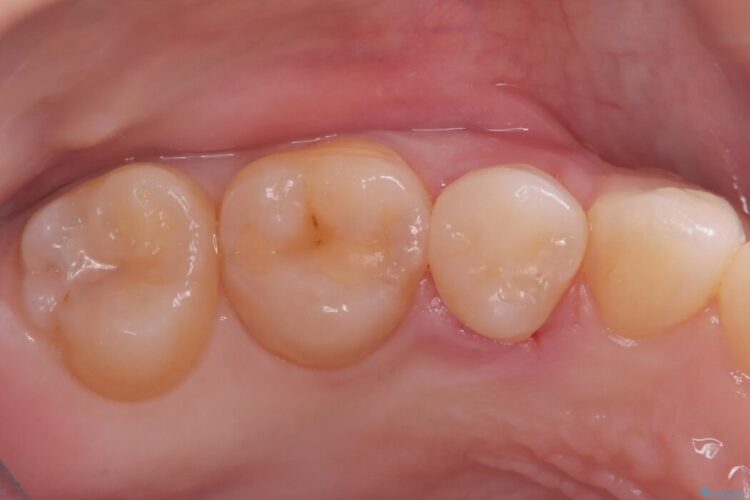

メタルフリー|全ての銀歯をセラミックへ

メタルフリー|全ての銀歯をセラミックへ ビフォー メタルフリー|全ての銀歯をセラミックへ アフター

口腔内の銀歯を全て無くし、白く健康的な状態にしたいとご来院された患者様です。